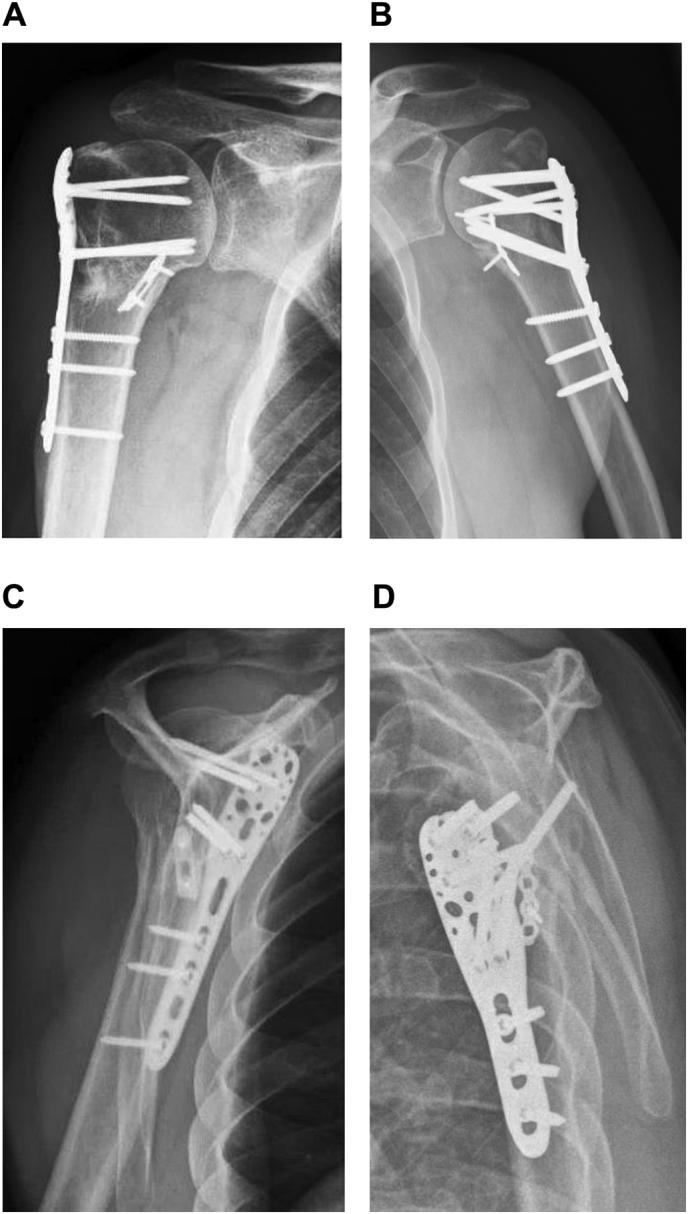

Proximal humerus fractures are common and approximately 20% of displaced fractures may benefit from surgery. A lack of medial support is found to be a predictor of failure after surgical fixation of proximal humerus fractures. The optimal technique for restoring the medial hinge is unclear. We describe two cases of patients with a dislocated 4-part humerus fracture treated with a locking plate and an additional small intramedullary plate to support the medial hinge. This technique is simple and allows for an enhanced stability of the medial hinge during and after surgery.

肱骨近端骨折很常见,约20%的移位骨折可能从手术中获益。研究发现,内侧支撑不足是肱骨近端骨折手术固定失败的一个预测因素。恢复内侧铰链的最佳技术尚不清楚。我们描述了两例四部分肱骨脱位骨折患者,采用锁定钢板和一块额外的小型髓内钢板来支撑内侧铰链进行治疗。该技术简单,能在手术中和手术后增强内侧铰链的稳定性。